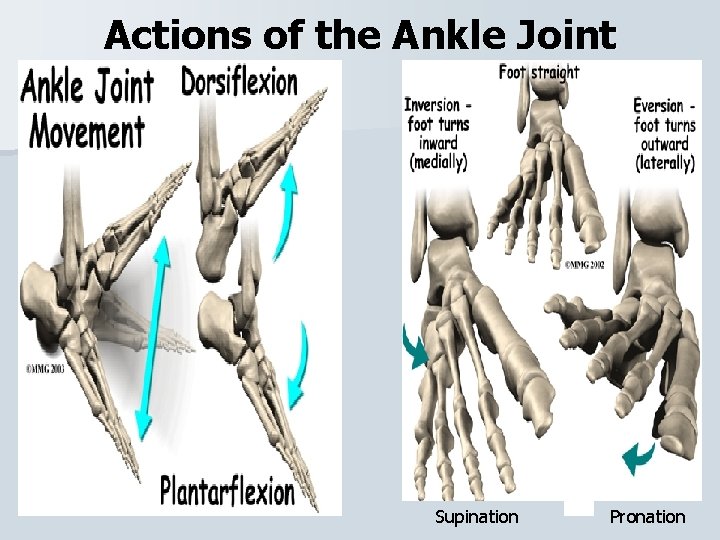

Actions of the Ankle Joint Supination Pronation